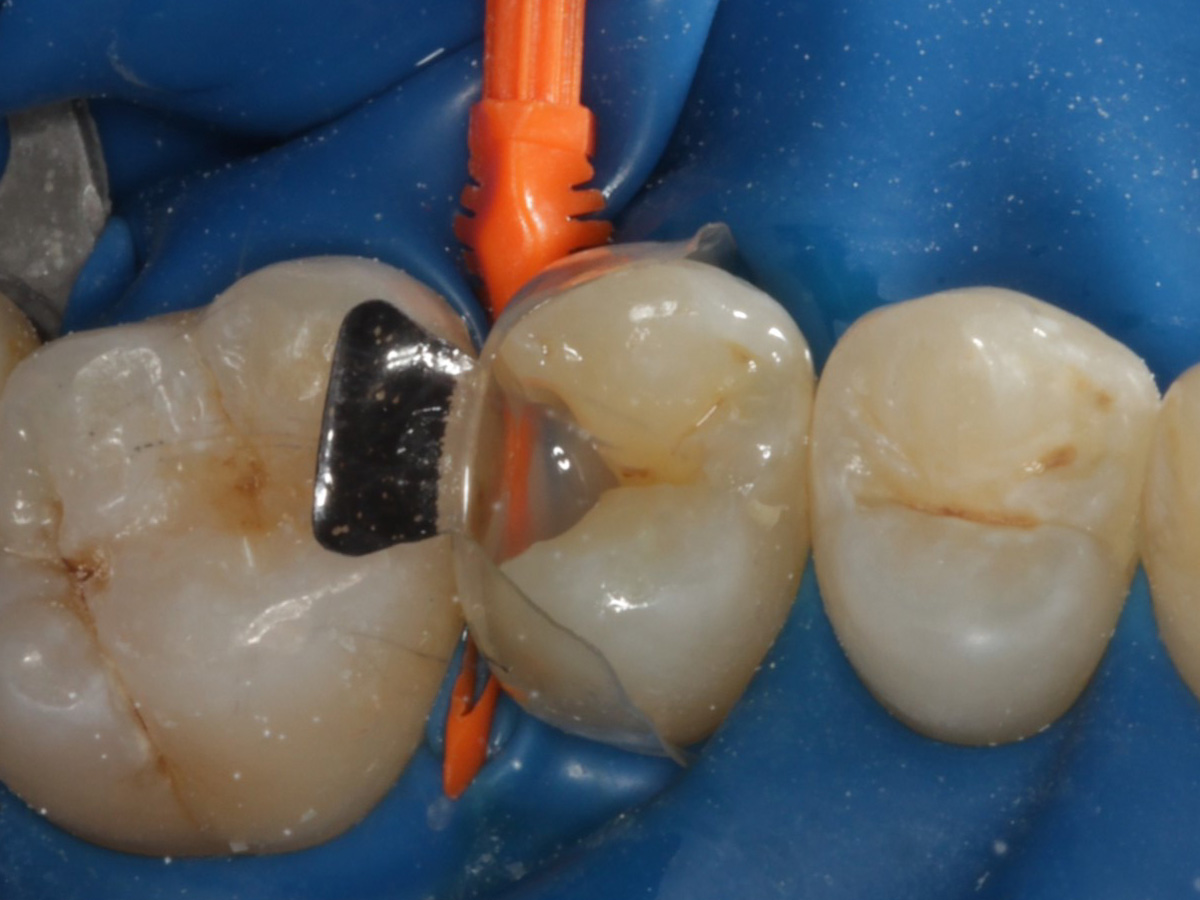

Abbildung 10

Nach Applikation der Matrize: Evolve Schwarz Prämolar- 7 mm; Schmelzätzung

Abbildung 11

Nach Spray und Trocknung der Kavität